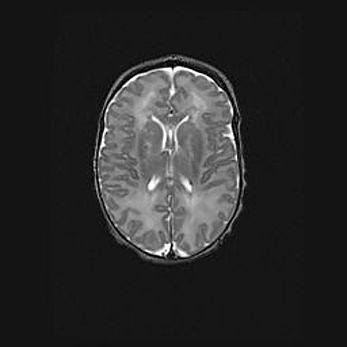

Множественные кисты обоих полушарий головного мозга, наибольшая из них в правой затылочной области. Ассиметричная атрофическая гидроцефалия.

Возраст: 7 месяцев

Вес: 5660 г

Пол: мужской

Окружность головы: 41,5 см

Срок гестации: 28-29 недель

Кисты головного мозга развиваются в результате многоочаговых некрозов вещества мозга и возникают вследствие перенесенной перинатальной инфекции, менингитов, энцефалитов, асфиксии, родовой травмы, расстройств мозгового кровообращения различного генеза. Образованию кист в веществе головного мозга плодов и новорожденных способствуют такие факторы, как высокое содержание в нем воды, недостаточная (или отсутствие) миелинизация и слабая астроглиальная реакция на повреждение.

Кисты могут сочетаться с гидроцефалией и другими поражениями головного мозга.